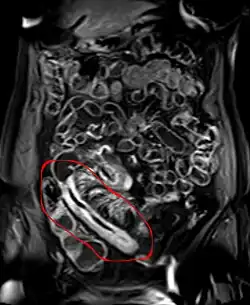

- Computertomografie oder Magnetresonanztomographie mit Kontrastmittel: Pflastersteinrelief, Fisteln, segmentale Stenosen, Darmwandverdickung

MR-Enteroklysma bei M. Crohn im terminalen Ileum: Deutliche Wandverdickung und Kontrastmittelaufnahme in dem befallenen Darmabschnitt. Dieser ist durch die Veränderungen auch atypisch gestreckt.